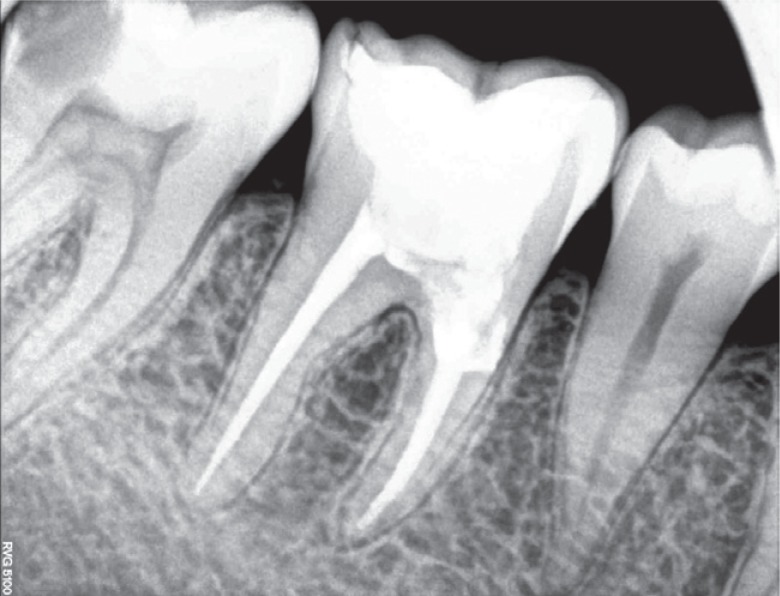

Figure 10Six month follow-up radiograph.

Figure 11One year follow-up radiograph showing appreciable healing in the periapical area.

Figure 12Twenty month follow-up radiograph.

9). The patient returned for follow-up after 6, 12, and 20 months, and the radiographs revealed appreciable healing in the periapical area (

Figures 10,

11,

12,

13).